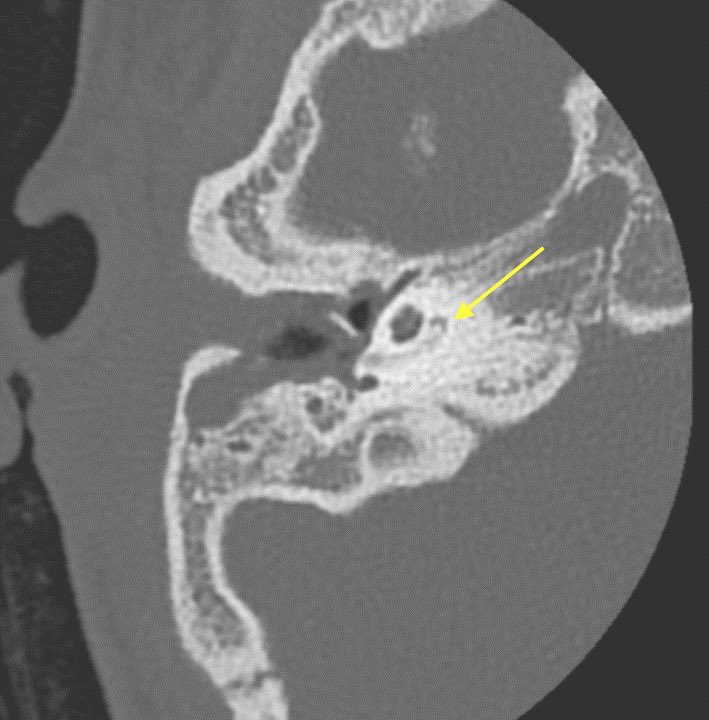

▶️MR: normally the membranous labyrinth should be high signal on T2 (normal left side with arrows) but the right side has lost the high signal due to ossification